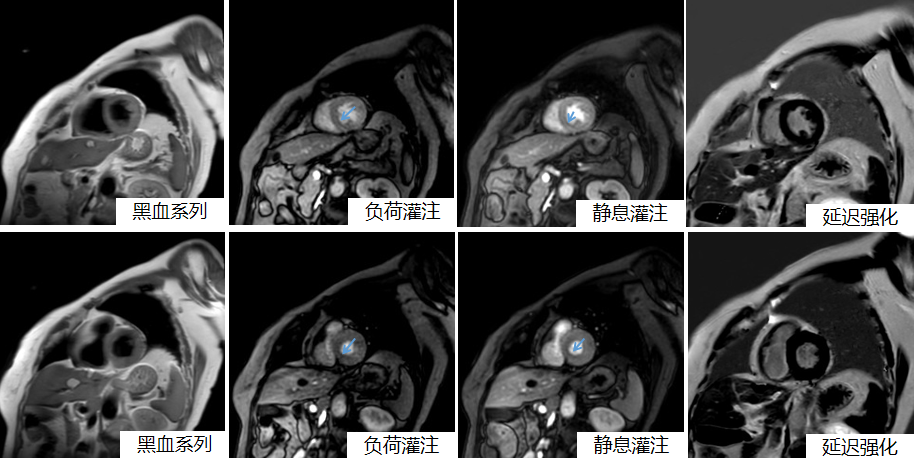

杨艳蓉主治医生经过分析图像,发现患者静息与负荷心肌灌注显示左心室多节段可见心内膜下灌注缺损,延迟强化未见异常(图1),提示患者心肌存在微循环障碍,这也解释了患者心外膜冠状动脉主要分支未见明显狭窄,仍反复出现胸闷、胸痛等症状,患者高血压病史已10年,血压最高170/100mmHg,而导致心肌微循环障碍。

图1